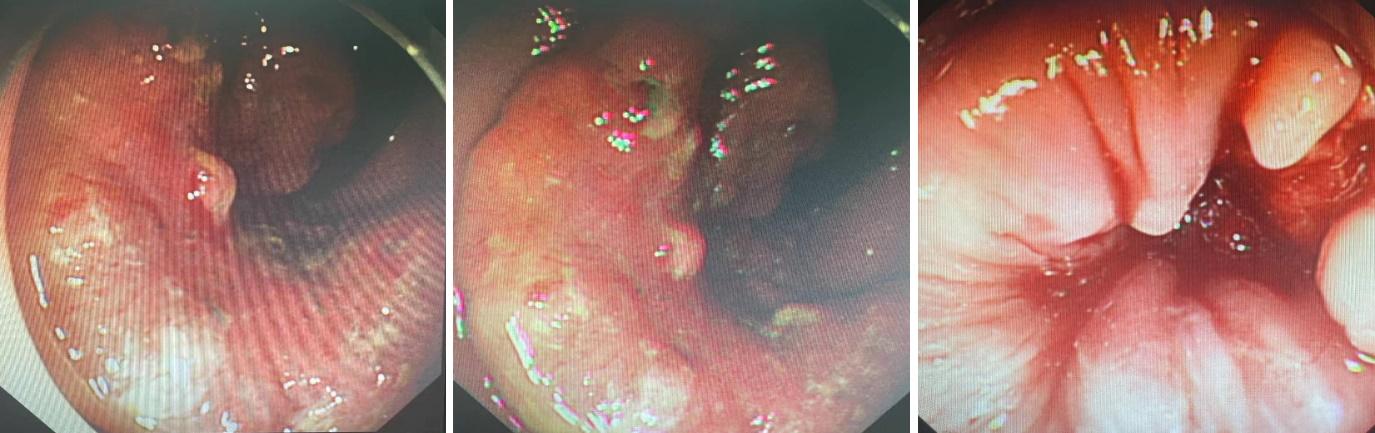

▲肠镜检查可见肿瘤已邻近齿状线